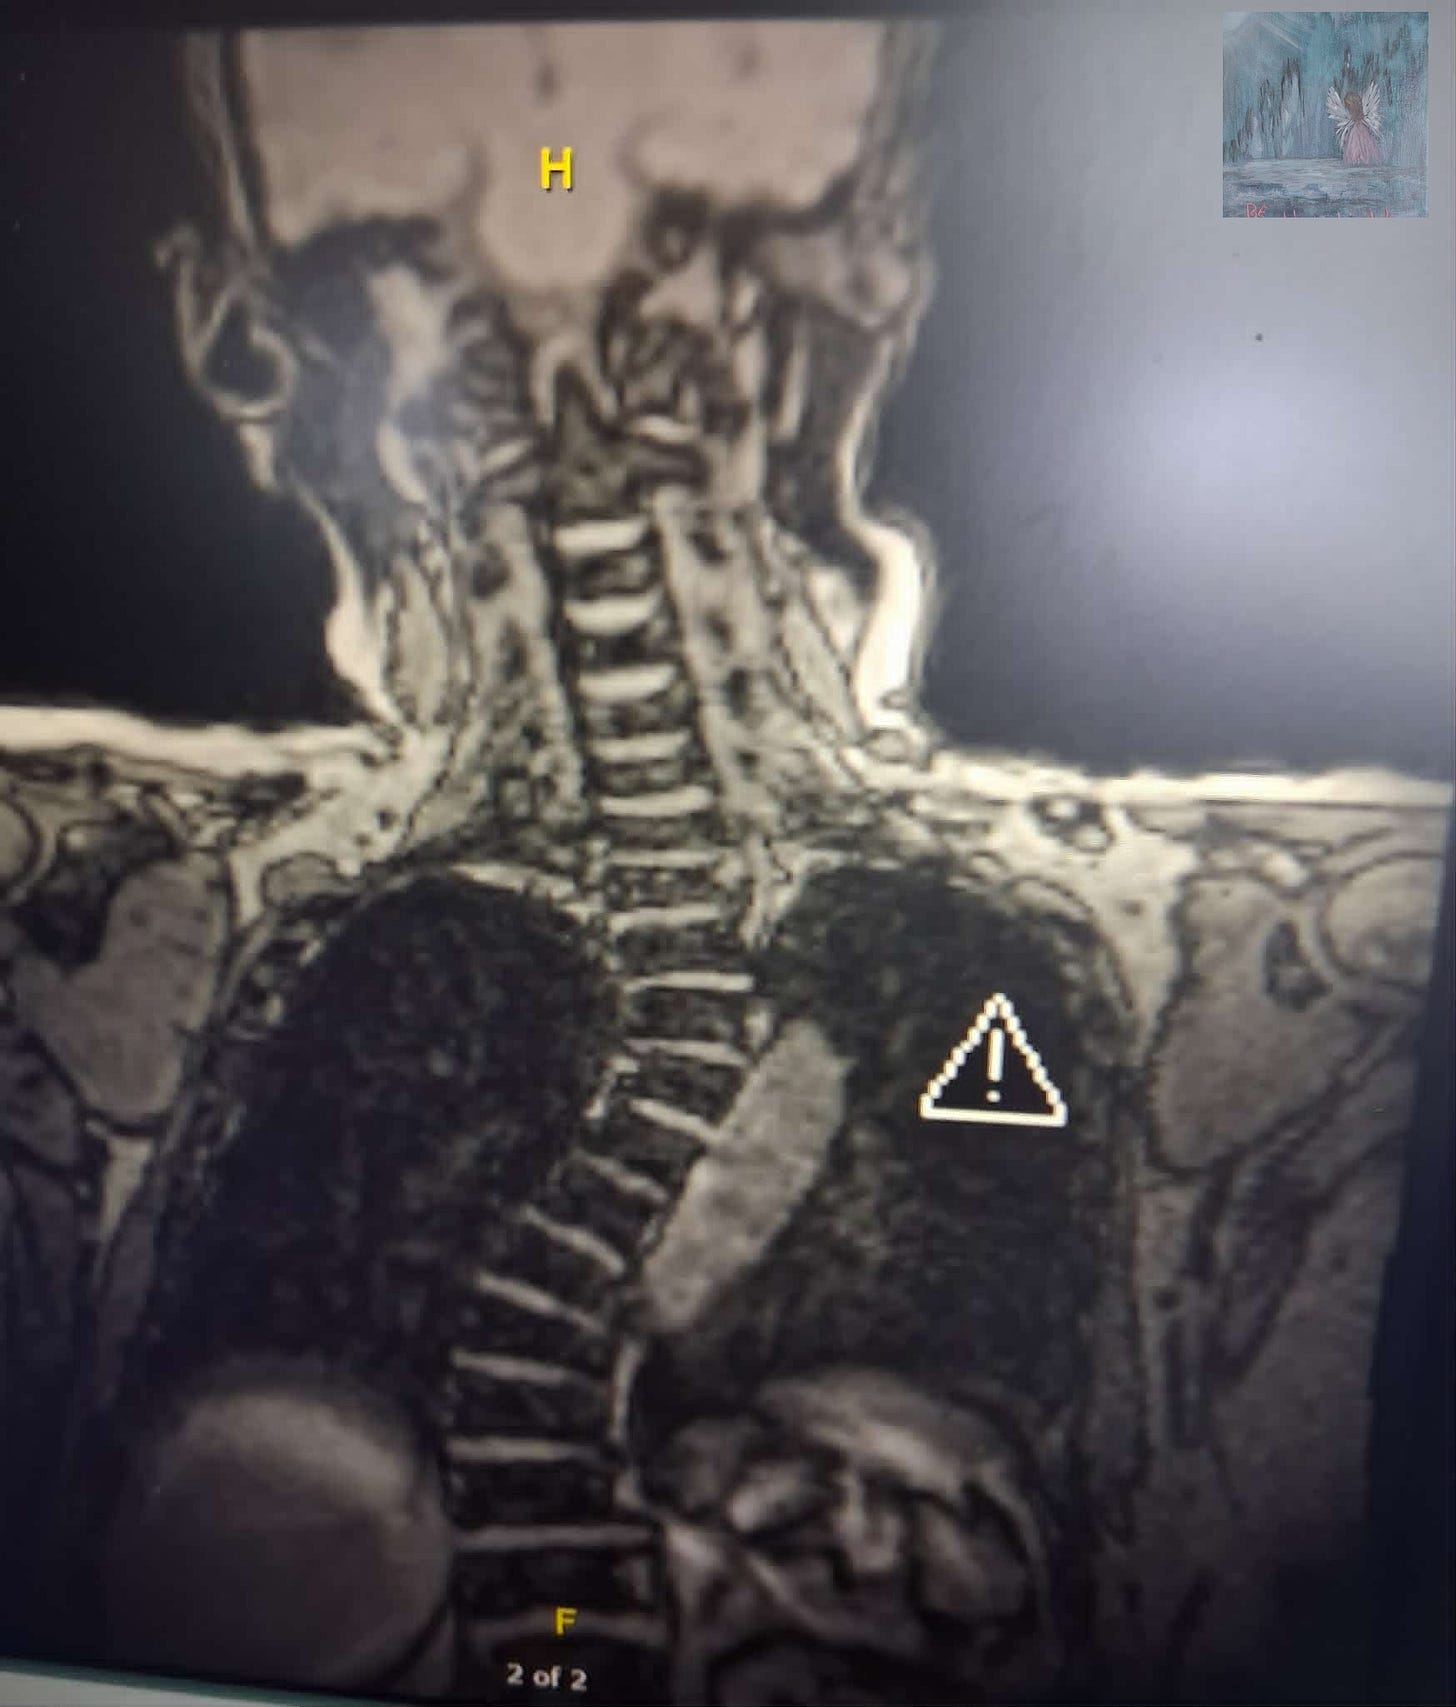

Below is one of the MRI images of me. Yup the inner me 😉😂As you can see I`m a little twisted. I think that`s where I draw my humor from.